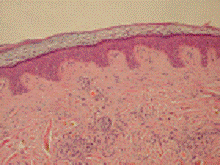

Микроскопия в области шеи

Гистологическая картина себорейного

дерматита